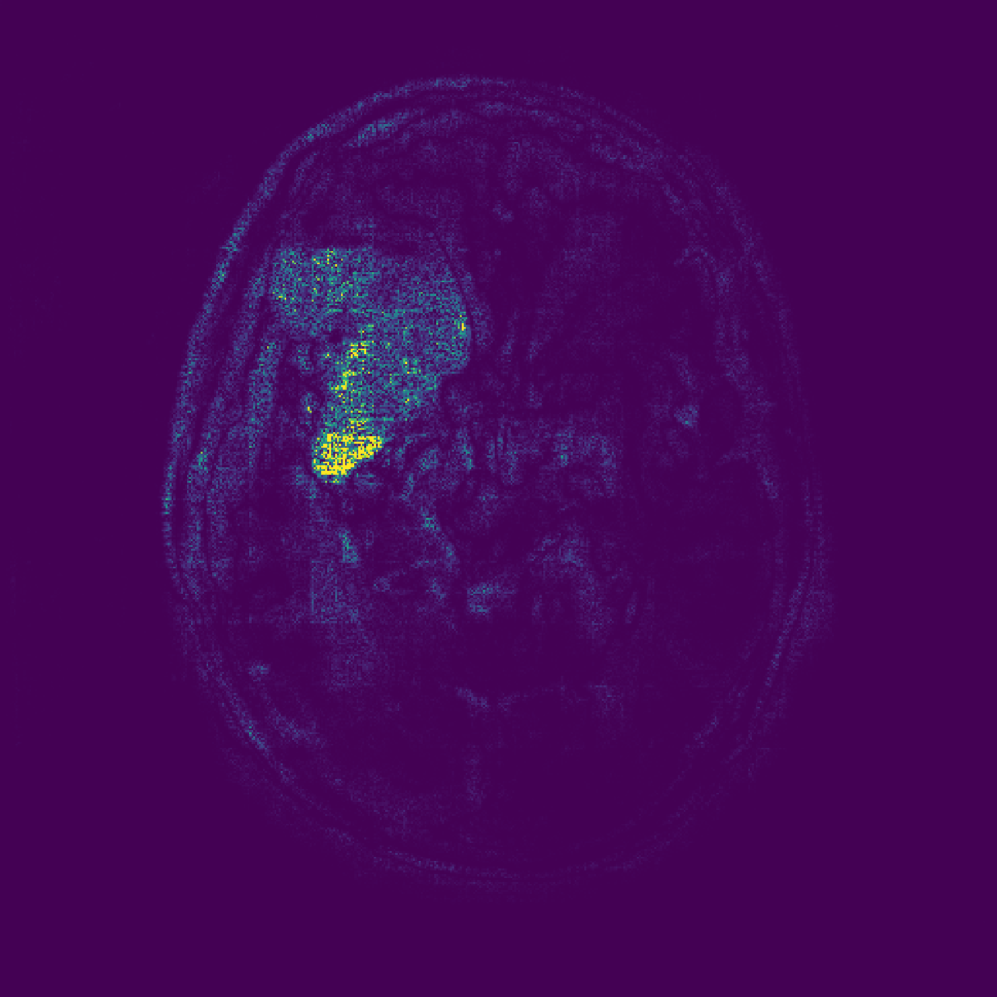

Figure 3: Examples of attributions obtained using different baselines. Typical colormaps for the respective domains are used (i.e. blue\rightarrowred for the Manometry data set and black\rightarrowwhite for the other two). For EG and EG (CF) we show the mean of the sampled baselines, providing a single representation for illustration purposes.

We evaluate the baselines on three medical data sets containing class labels and segmentation masks for pathological region localization. Images are resized to 512×512512\times 512 and normalized to [0,1][0,1]. Evaluation is based on correctly classified, pathological test samples with available segmentation masks. Dataset sizes are detailed in Table 5. Train/test splits are either predefined (Chest X-ray, Brain MRI) or randomly selected (Manometry). For a qualitative impression, Figure 5 shows an example input from each data set with corresponding attribution maps for the various baselines we compare.

Brain MRI  The data set333Available at: https://www.kaggle.com/datasets/mateuszbuda/lgg-mri-segmentation/data comprises brain MRIs for tumor classification and segmentation tasks Buda et al. (2019). The data set contains two classes, comprising normal and pathological samples, with the tumors mostly visible as bright regions due to contrast agent.